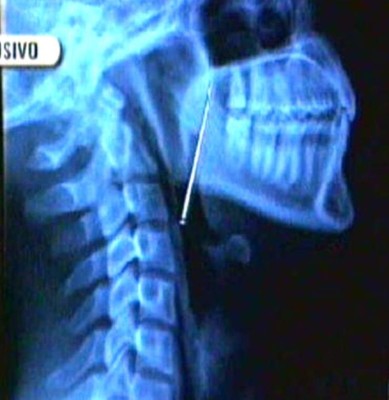

Cuando su madre Angelina Mayta la llevó al hospital, la radiografía que le hicieron reveló que el objeto se encontraba en su garganta.

Los médicos le indicaron que la menor corre peligro, pues si el alfiler golpease algún órgano, podría ocasionar una hemorragia e incluso la muerte.